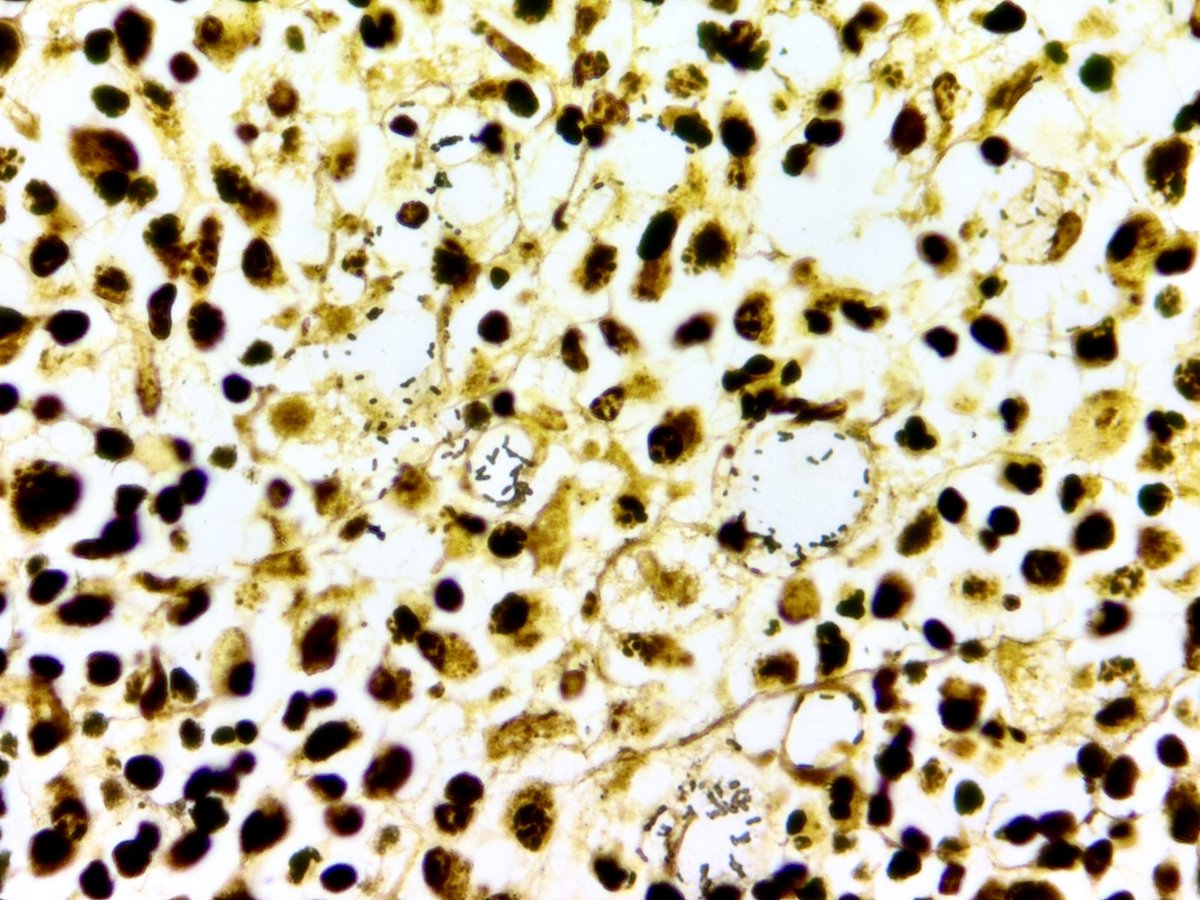

Not something you see everyday! Rhinoscleroma - 👃Nasal cavity mass 🤓Mickulicz cells are the classic clear histiocytes seen (tons of them here) 💥Causative organism - Klebsiella rhinoscleromatis Check out that Warthin Starry! 🤩 #ENTpath #Headandneckpathology #pathresidents

Not something you see everyday! Rhinoscleroma -

👃Nasal cavity mass

🤓Mickulicz cells are the classic clear histiocytes seen (tons of them here)

💥Causative organism - Klebsiella rhinoscleromatis

Check out that Warthin Starry! 🤩

#ENTpath #Headandneckpathology #pathresidents